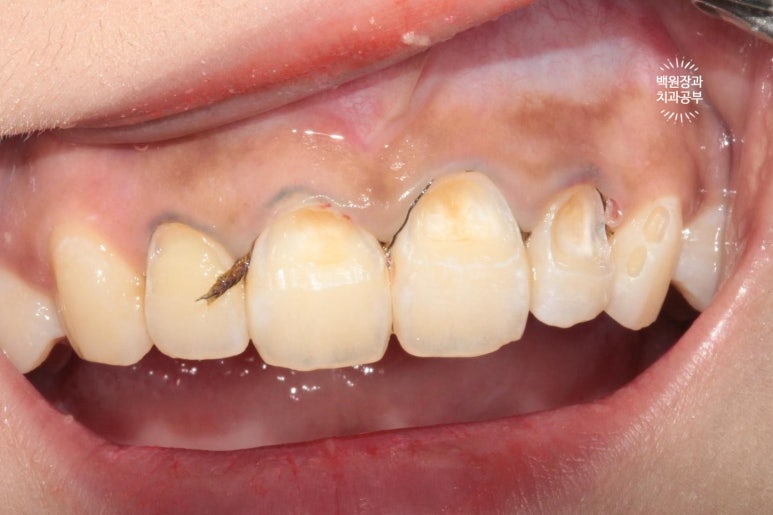

위 사진은 충치를 갓 제거하고 나서의 사집입니다.

충치가 넓기도 하였지만, 자연스러운 색조 재현을 위해 널찍하게 치아삭제를 시행하였습니다.

bevel도 길게 주고..

잇몸의 하방에 삽입되어 있는 코드는 충치치료 직후 제거될 예정입니다.

깊이 있는 충치가 잘 보이게 하기 위함이죠.